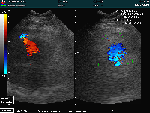

心エコー

(心臓超音波検査) |

超音波を使用した心臓の検査です。心臓の大きさや動きの検査を行います。弁の動きや血流に色を付けて血液の逆流の有無などの検査を行うことも出来ます。 |